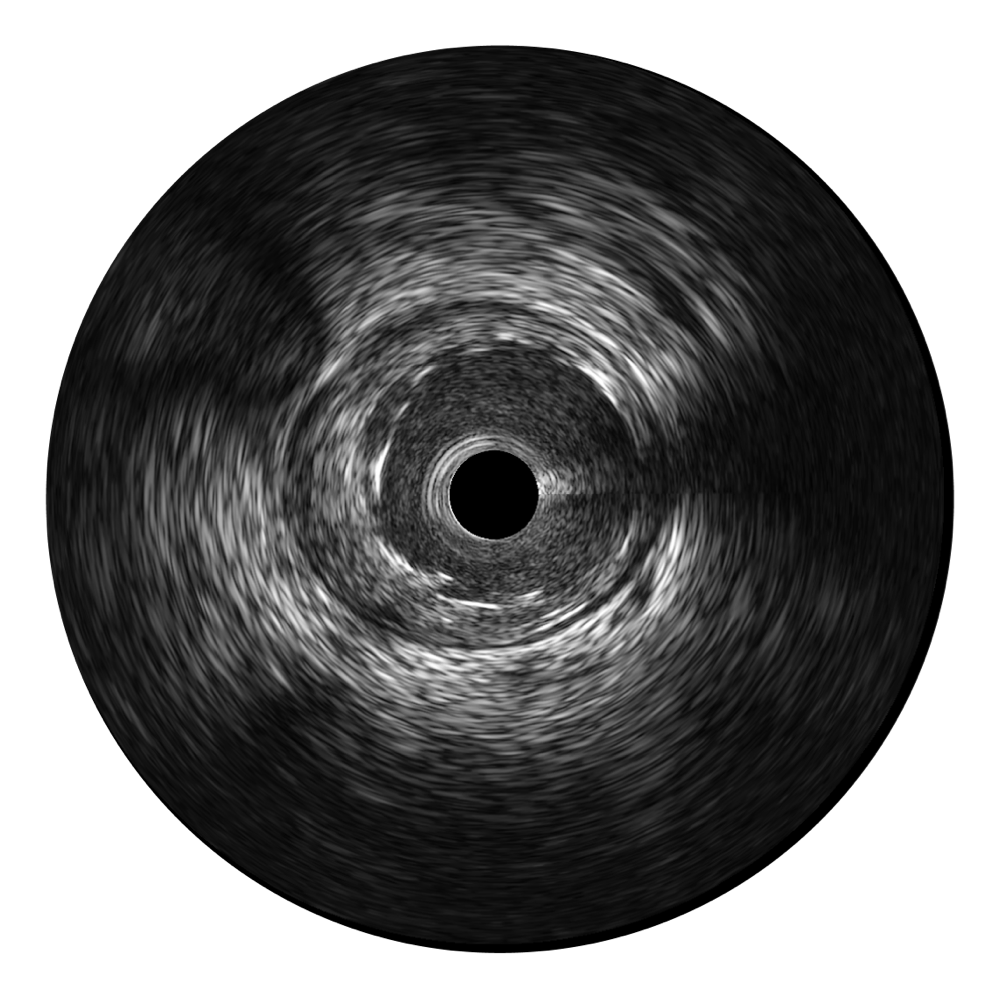

• 传统IVUS图像

对比传统IVUS导管成像,环球UG官网宽频IVUS图像的近场支架梁显影更细腻,远场中膜外血管仍清晰可辨,兼顾远中近,兼顾分辨力与穿透深度